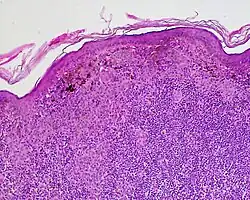

Halo nevi are also known as Sutton's nevi, or leukoderma acquisitum centrifugum.[2] Halo nevi are named such because they are a mole (nevus) that is surrounded by an area of depigmentation that resembles a halo.

The formation of a halo surrounding a nevi is believed to occur when certain white blood cells called CD8+ T lymphocytes destroy the pigment-producing cells of the skin (melanocytes).[4] The cause for the attack is unknown.[5]